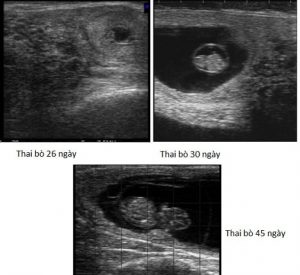

Thông thường trên lâm sàng, chẩn đoán có thai ở bò thường được tiến hành bằng phương pháp khám qua trực tràng và siêu âm. Ưu điểm của phương pháp siêu âm, so với khám qua trực tràng, đó là, siêu âm là một phương pháp ít xâm lấn hơn; do vậy, rất an toàn khi dùng siêu âm để chẩn đoán có thai ở bò, giảm thiểu nguy cơ sảy thai. Ngoài ra, bằng phương pháp siêu âm, người ta có thể chẩn đoán có thai sớm hơn. Cụ thể, sau khi phối giống 26 ngày, là có thể biết bò có thai hay không. Trong khi đó, phương pháp chẩn đoán thai bằng tay thông qua trực tràng, với những bác sỹ thú y, kỹ thuật viên có kinh nghiệm thì họ cho rằng, có thể khám thai từ ngày thứ 35, sau khi phối giống. Tuy nhiên, độ chính xác của kết quả sẽ không cao, mà thường thì phải khám ở ngày thứ 40-45, sau khi phối giống trở ra.

Bên cạnh việc chẩn đoán có thai sớm, và chính xác hơn so với phương pháp truyền thống là khám qua trực tràng. Với kỹ thuật siêu âm, người ta có thể chẩn đoán chính xác bào thai còn sống hay đã chết, thông qua việc quan sát tim thai đập. Với phương pháp khám bằng tay, chỉ xác định có thai hay không, còn không thể xác định được bào thai còn sống hay đã chết, ở giai đoạn đầu của quá trình mang thai. Cuối cùng, trong chẩn đoán có thai sớm ở bò, thì dùng siêu âm còn phân biệt được trường hợp, là có thai với viêm nội mạc tử cung tích dịch, tích mủ, làm cho tử cung cũng căng lên, khi khám bằng tay dễ nhầm lẫn là có thai. Tuy nhiên, dùng phương pháp siêu âm, thì trường hợp này phân biệt rất dễ dàng, bằng việc xác định tử cung có bào thai hay không.

Hình ảnh bào thai bò